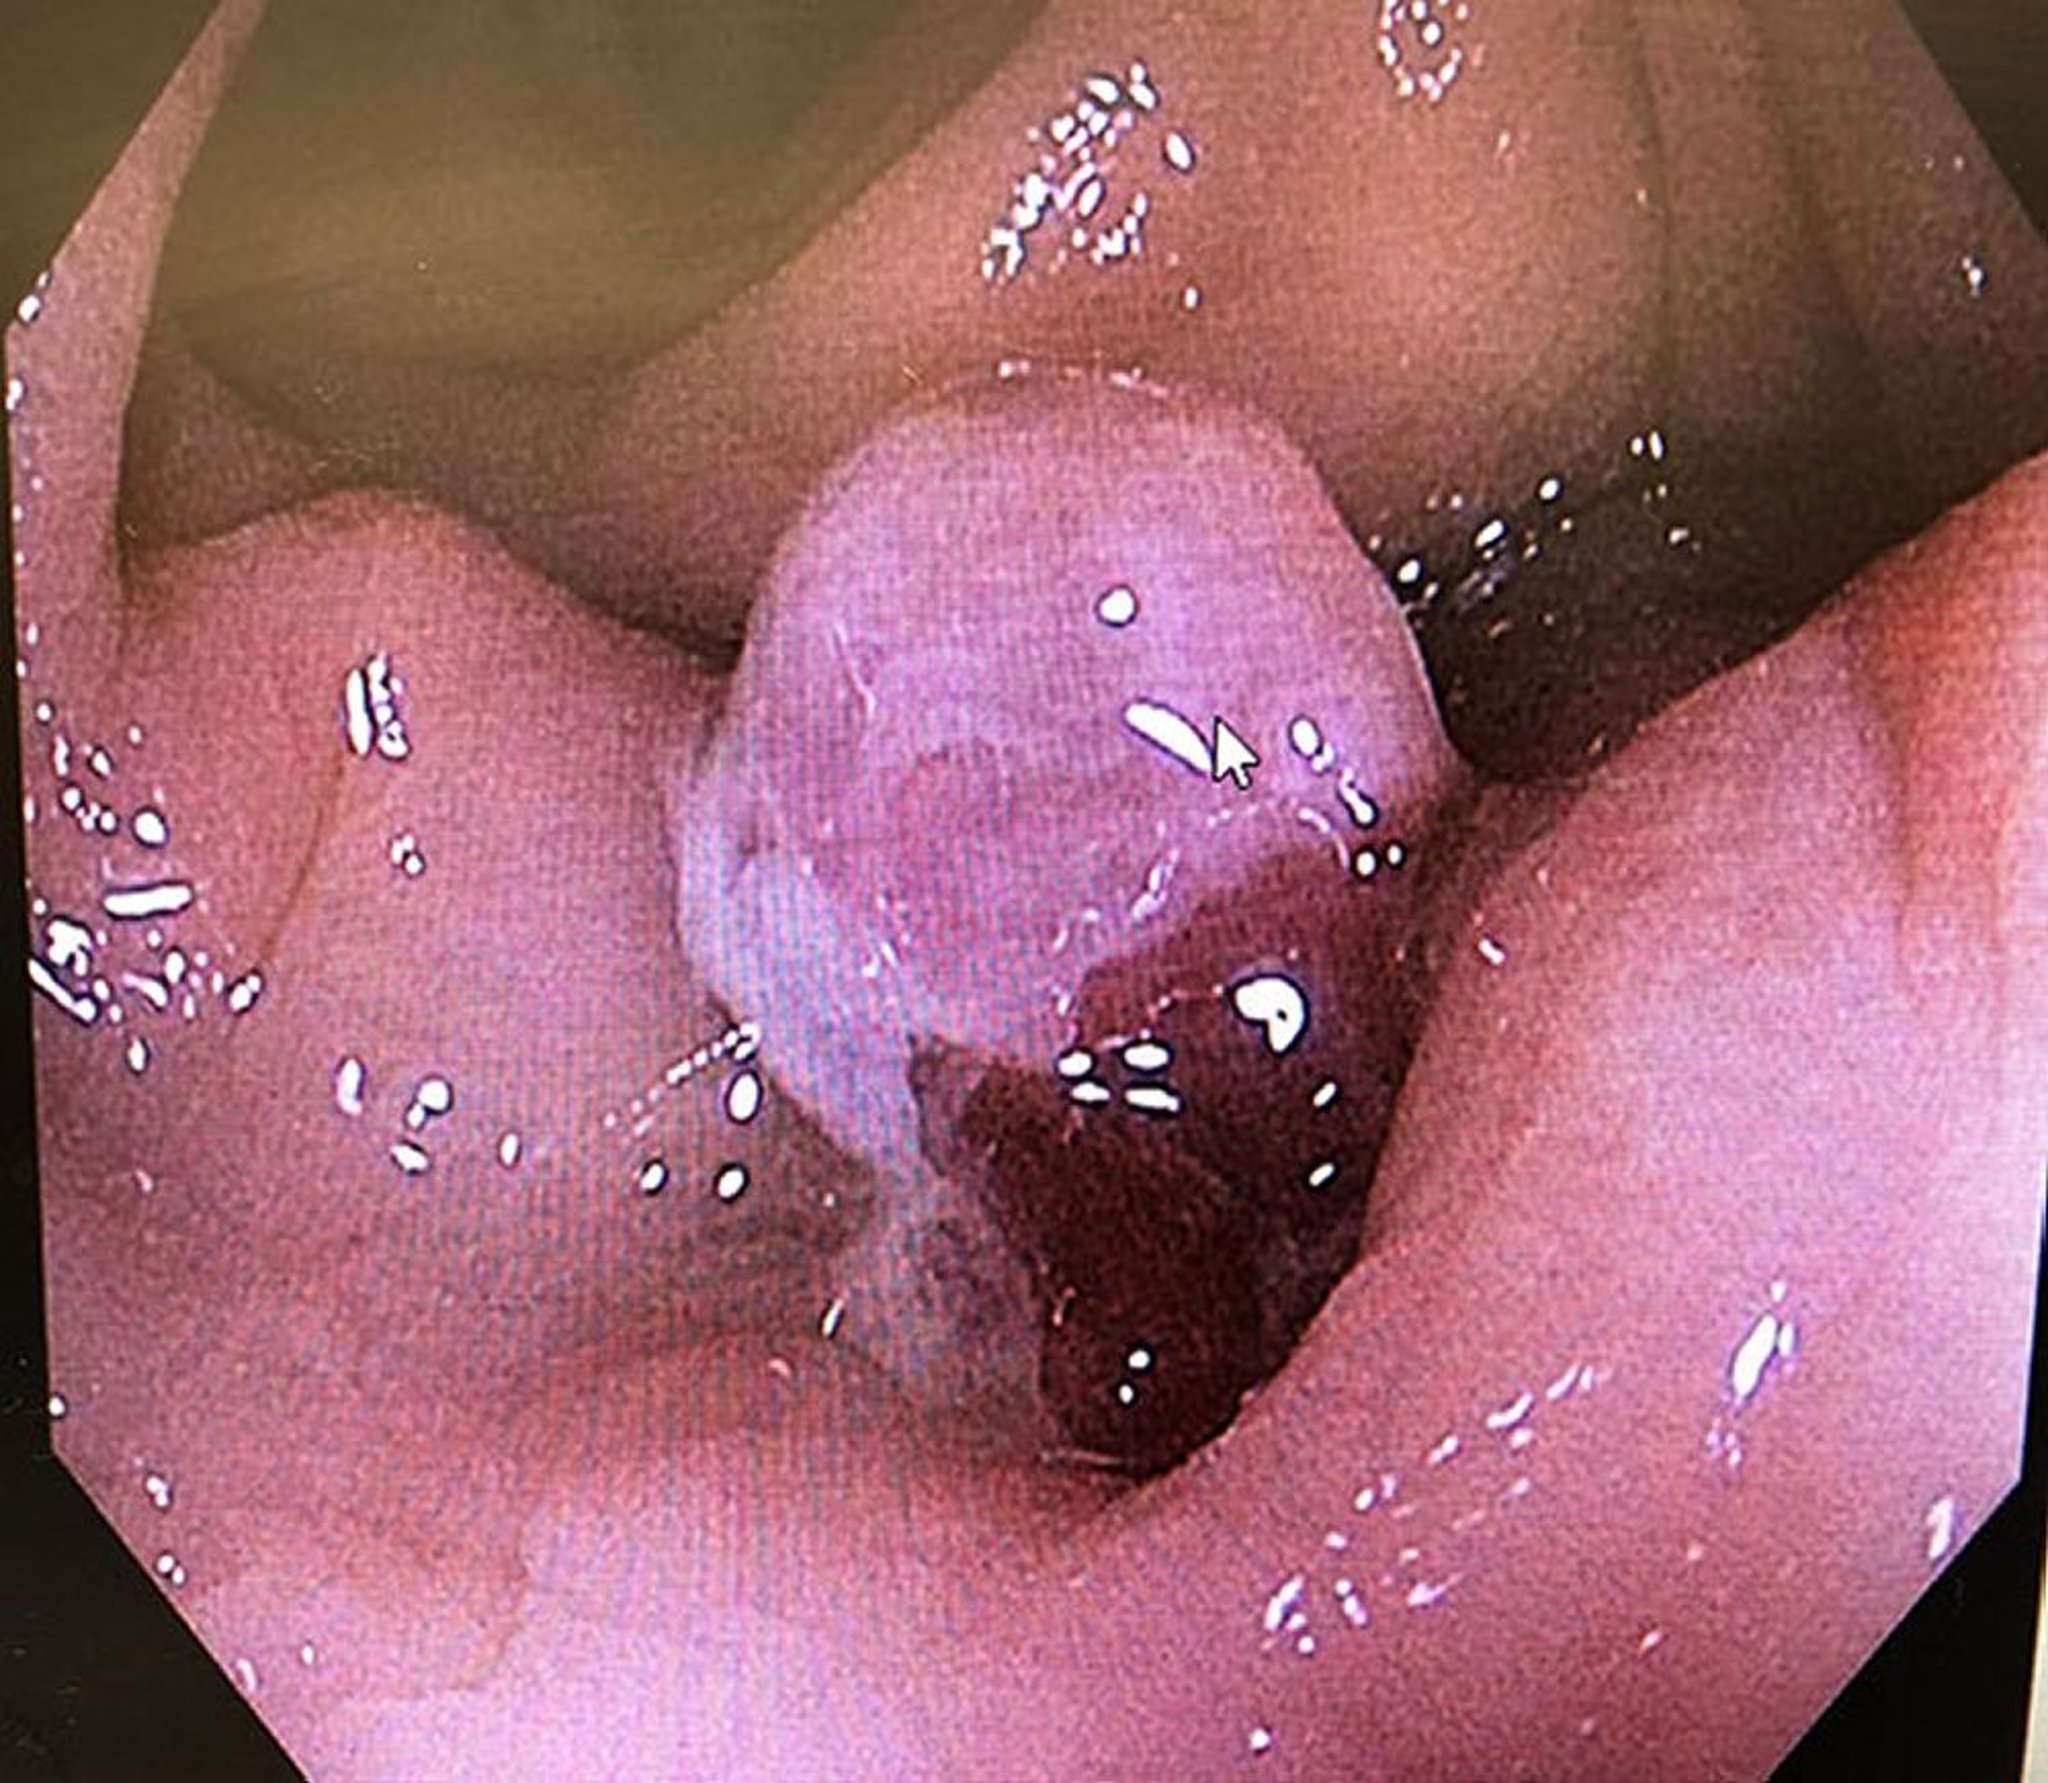

Cette image montre un tissu de granulation (pointe de flèche) dépassant d'un diverticule unique enflammé avec une diverticulite.

Photo courtesy of Drs. Joel A. Baum and Rafael A. Ching Companioni.